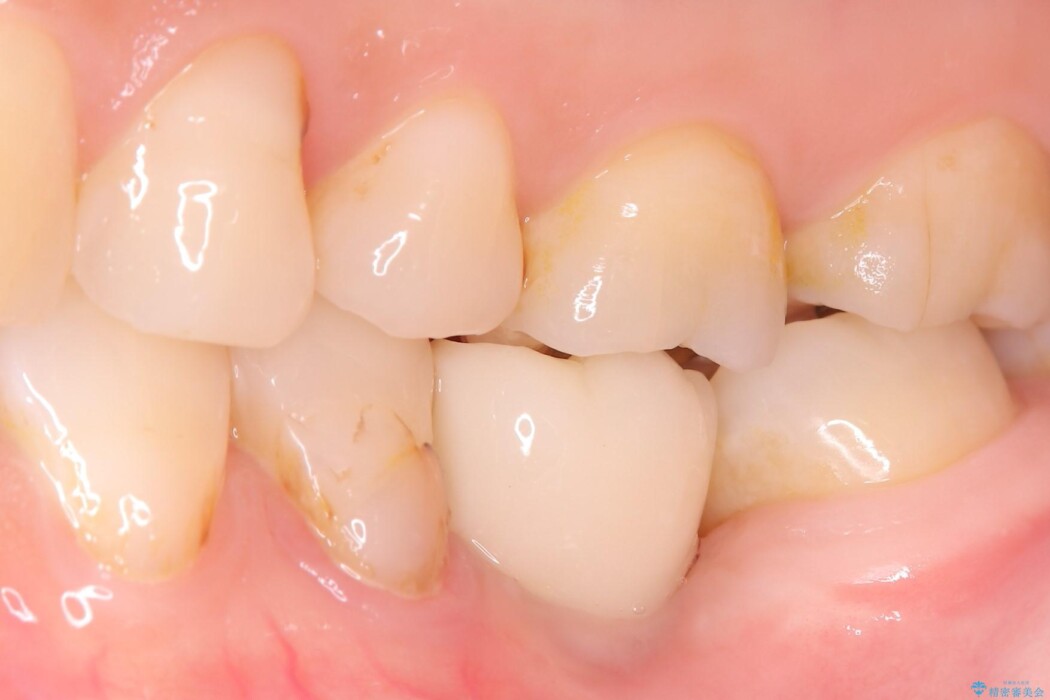

左下奥歯の抜歯後、長期間放置していたために、周囲の骨が吸収してしまいました。 特に垂直的な高さが不足しており、通常の術式ではインプラント埋入が難しい状態でした。

精密検査の結果、高さに制限はあるが厚みは十分に確保されていることが確認されました。

骨を増やす治療は行わず、残っている骨を最大限に活用し治療を行うこととしました。